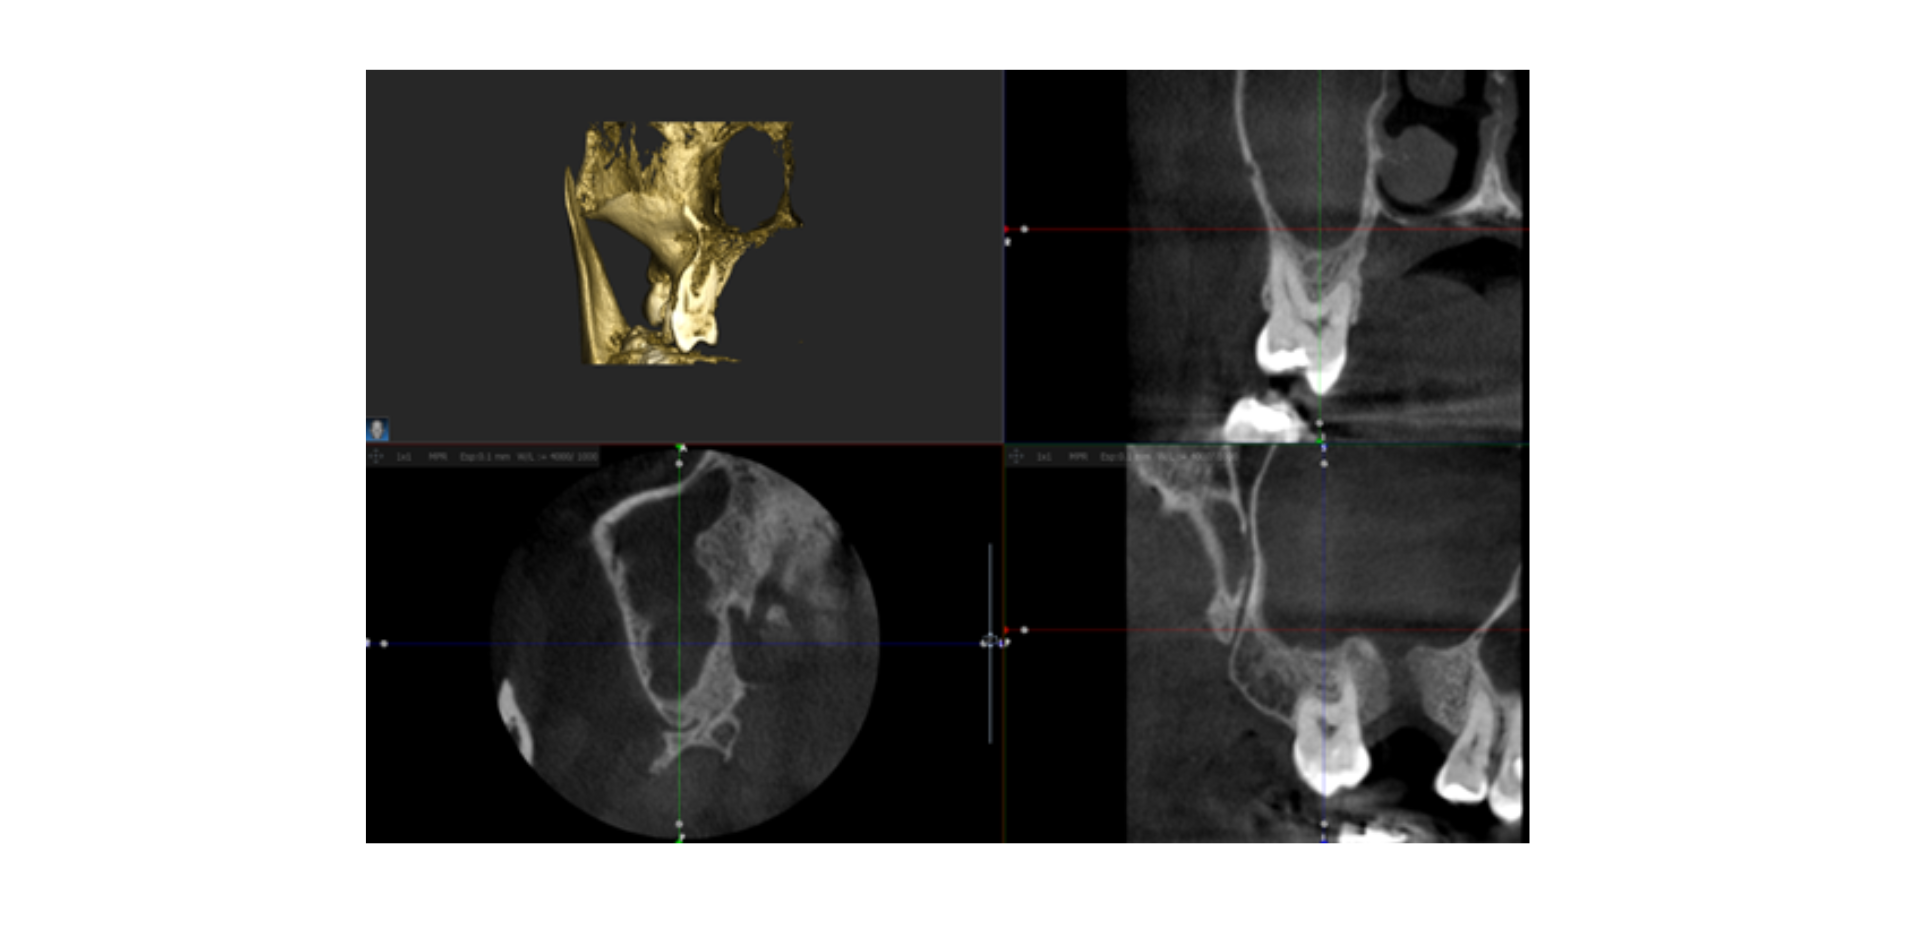

- Colocación de implantes: migración de implante al seno maxilar/ perforación de la membrana sinusal...

- Implante o pieza dental migrada al seno

Bloque 4: Casos clínicos y conclusiones